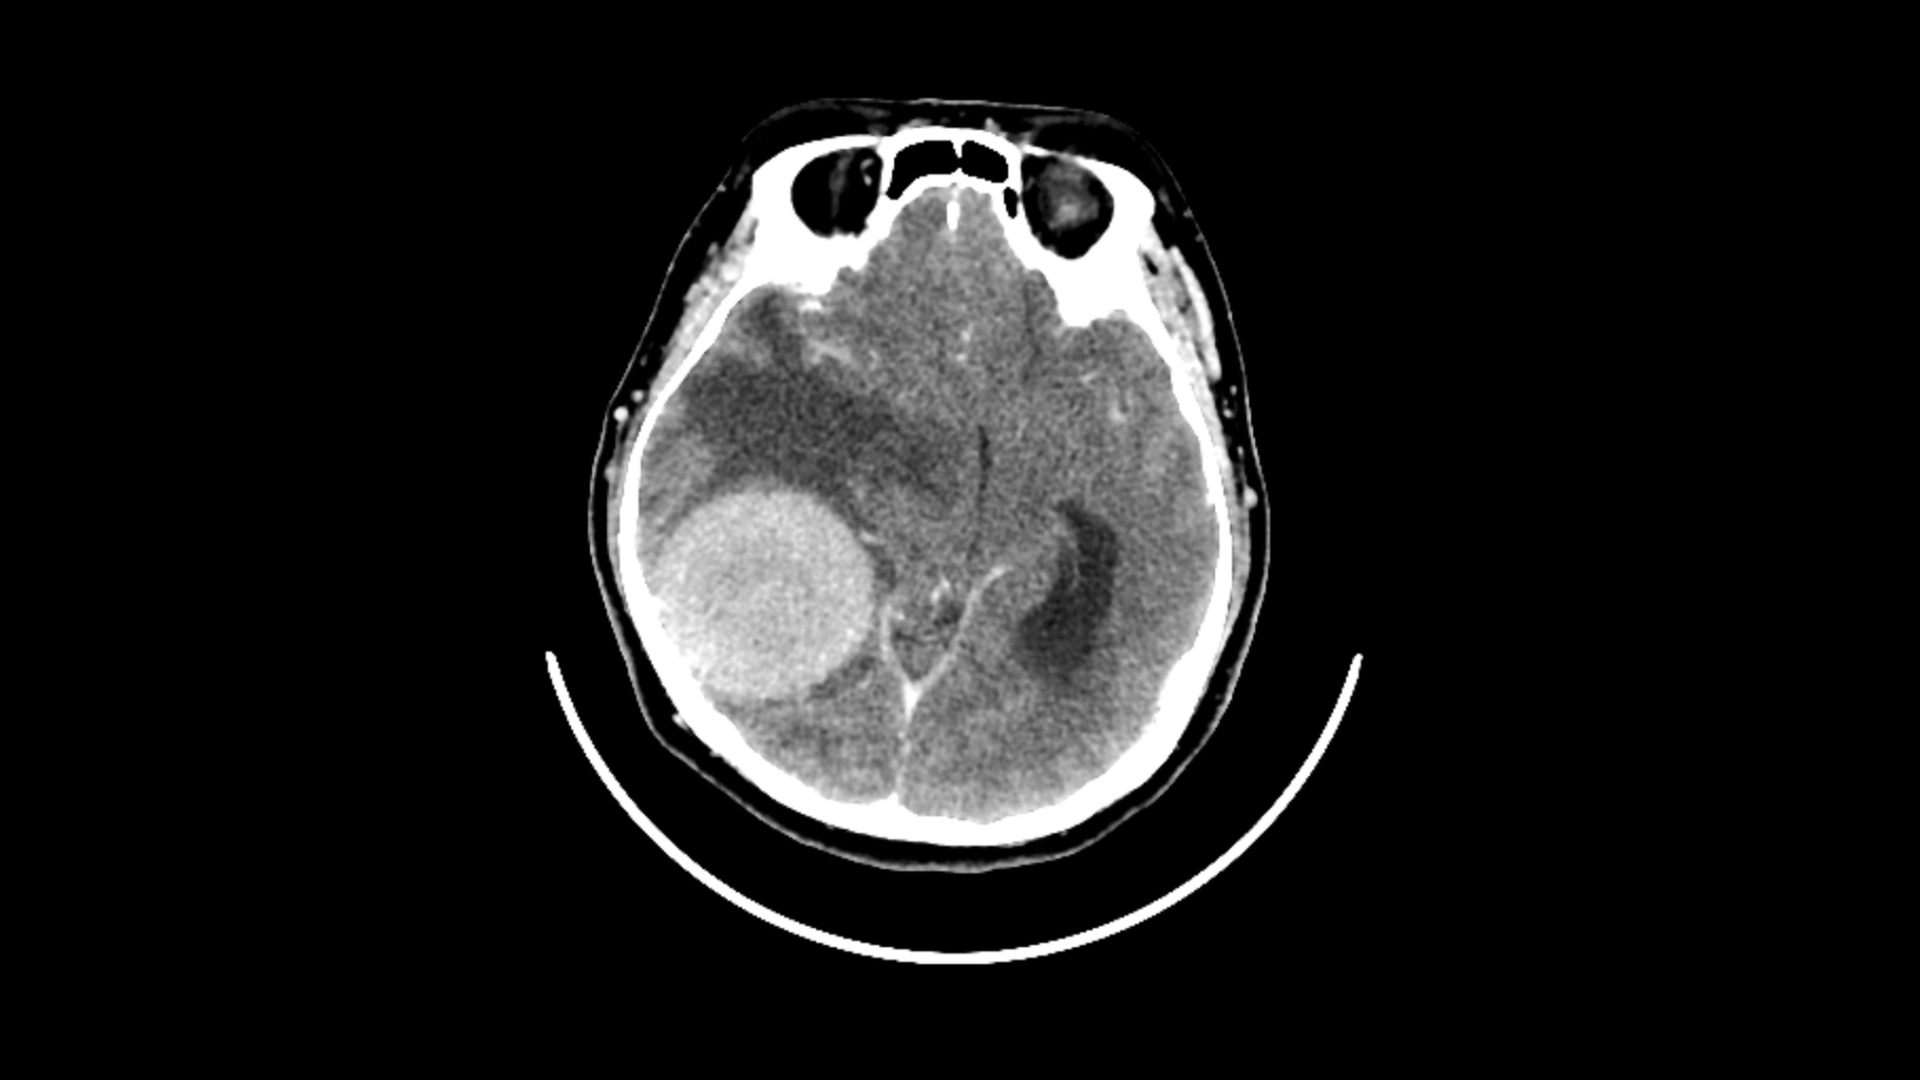

دراسة صادمة.. القلق والدوار يرتبطان بأورام الدماغ!

توصلت دراسة حديثة إلى وجود علاقة بين القلق والدوخة من جهة، والأورام الدماغية الحميدة من جهة أخرى....